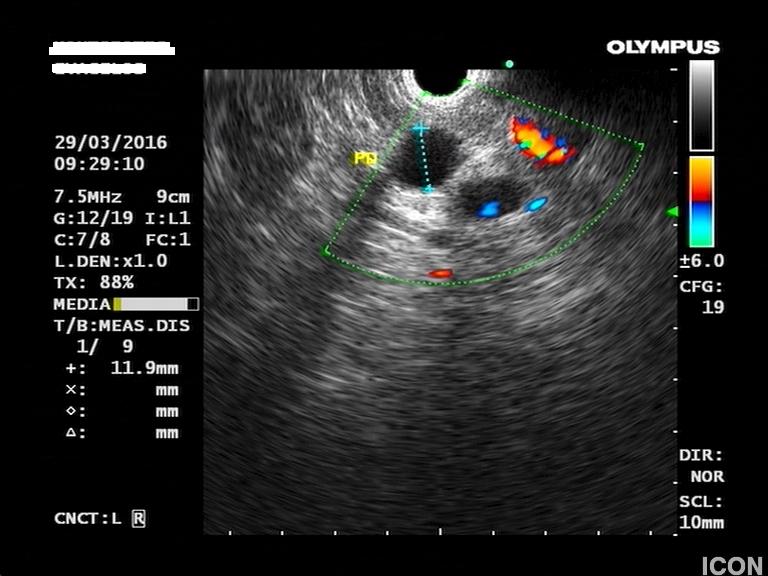

Ο ασθενής υποβλήθηκε σε ενδοσκοπικό υπέρηχο που έδειξε μια υποηχοϊκή μάζα διαμέτρου 21 χιλιοστών, με σαφή όρια, στην παγκρεατική κεφαλή και μεγάλη διάταση του χοληδόχου πόρου και του παγκρεατικού πόρου (διάμετρος 12 χιλιοστά).

Η μάζα είχε ξεκάθαρο διαχωριστικό όριο λίπους από την άνω μεσεντέριο φλέβα και δεν διηθούσε κανένα άλλο μεγάλο αγγείο της περιοχής (πυλαία φλέβα, σπληνοπυλαία συμβολή και αρτηρίες). Έγινε βιοψία με λεπτή βελόνη (FNA Χ3) και το κυτταρολογικό υλικό ήταν θετικό για αδενοκαρκίνωμα παγκρέατος. Το νεόπλασμα κρίθηκε χειρουργήσιμο και ο ασθενής υποβλήθηκε σε επέμβαση Whipple κατά την οποία αφαιρέθηκε πλήρως η παγκρεατική κεφαλή και ο όγκος σε υγιή όρια αλλά και 12 λεμφαδένες που ήταν όλοι αρνητικοί για κακοήθεια. Ο ασθενής υποβάλλεται σε συμπληρωματική χημειοθεραπεία.

Ενδοσκοπικός υπέρηχος: διάταση παγκρεατικού πόρου